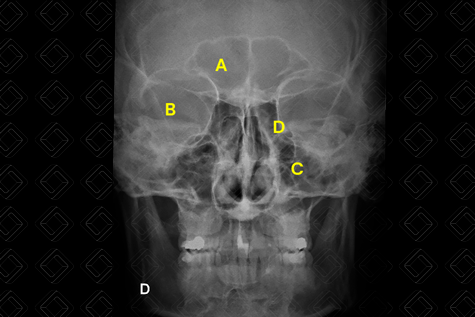

Texto alternativo para a imagem Figura 3. Radiografia dos seios paranasais mento-naso (Waters). Créditos: Dra. Elazir Mota - Rio de Janeiro/RJ

Legenda das siglas (figura 3): A = assoalho dos seios maxilares (é possível observar a presença de duas imagens lobuladas bilateralmente, sendo maior à esquerda - seta vermelha - e podendo representar cistos de retenção); B = borda orbital inferior.

• Incidência de Waters (posteroanterior em mento-naso): Pescoço esticado, colocar o queixo e o nariz contra a superfície da mesa / Bucky vertical. Avaliar os seios maxilares com a parede inferior visualizada sem superposição dos processos alveolares e cristas petrosas, a borda orbital inferior e uma posição oblíqua dos seios frontais. (Vide Figura 3 acima, em "Como Solicitar") ;